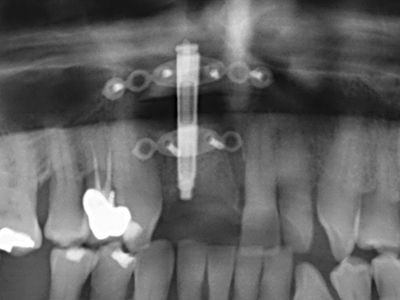

Fig. 11: la panoramica postoperatoria mostra l'accrescimento verticale e il rialzo del pavimento sinusale.

Fig. 12: dopo sei mesi di processo di guarigione, la cresta alveolare è vitale e sufficientemente dimensionata in tutti i piani.